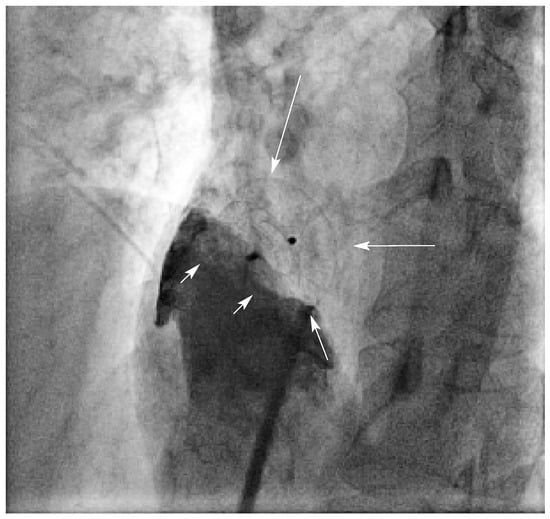

Abbildung 1. Spontaner Kontrastmittel-Übertritt durch das OFO in den linken Vorhof (Pfeile).

Abbildung 2. Kein Rest-Shunt nach Plazierung des Verschluss-Schirmes (Pfeile). Kontrastmittel-Injektion in den rechten Vorhof (kleine Pfeile).

Im ersten halben Jahr 2004 hat der Autor bei 11 Patienten ein OFO perkutan nach den oben erwähnten Kriterien verschlossen (Abb. 2). Davon litten 4 Patientinnen (38-, 39-, 44und 47jährig) seit Jahren an Migräne, wobei die Indikation zum OFO-Verschluss nicht aufgrund der Migränesymptomatik gestellt wurde. Sowohl unmittelbar vor und nach Plazierung des Amplatzer-PFO-Occluders™ als auch anlässlich der nach 3–6 Monaten durchgeführten Kontrollen wurden keine Rest-Shunts, weder mittels «Bubbles»-Kontrastnoch mittels Farbdoppler-Untersuchung nachgewiesen (Abb. 3).